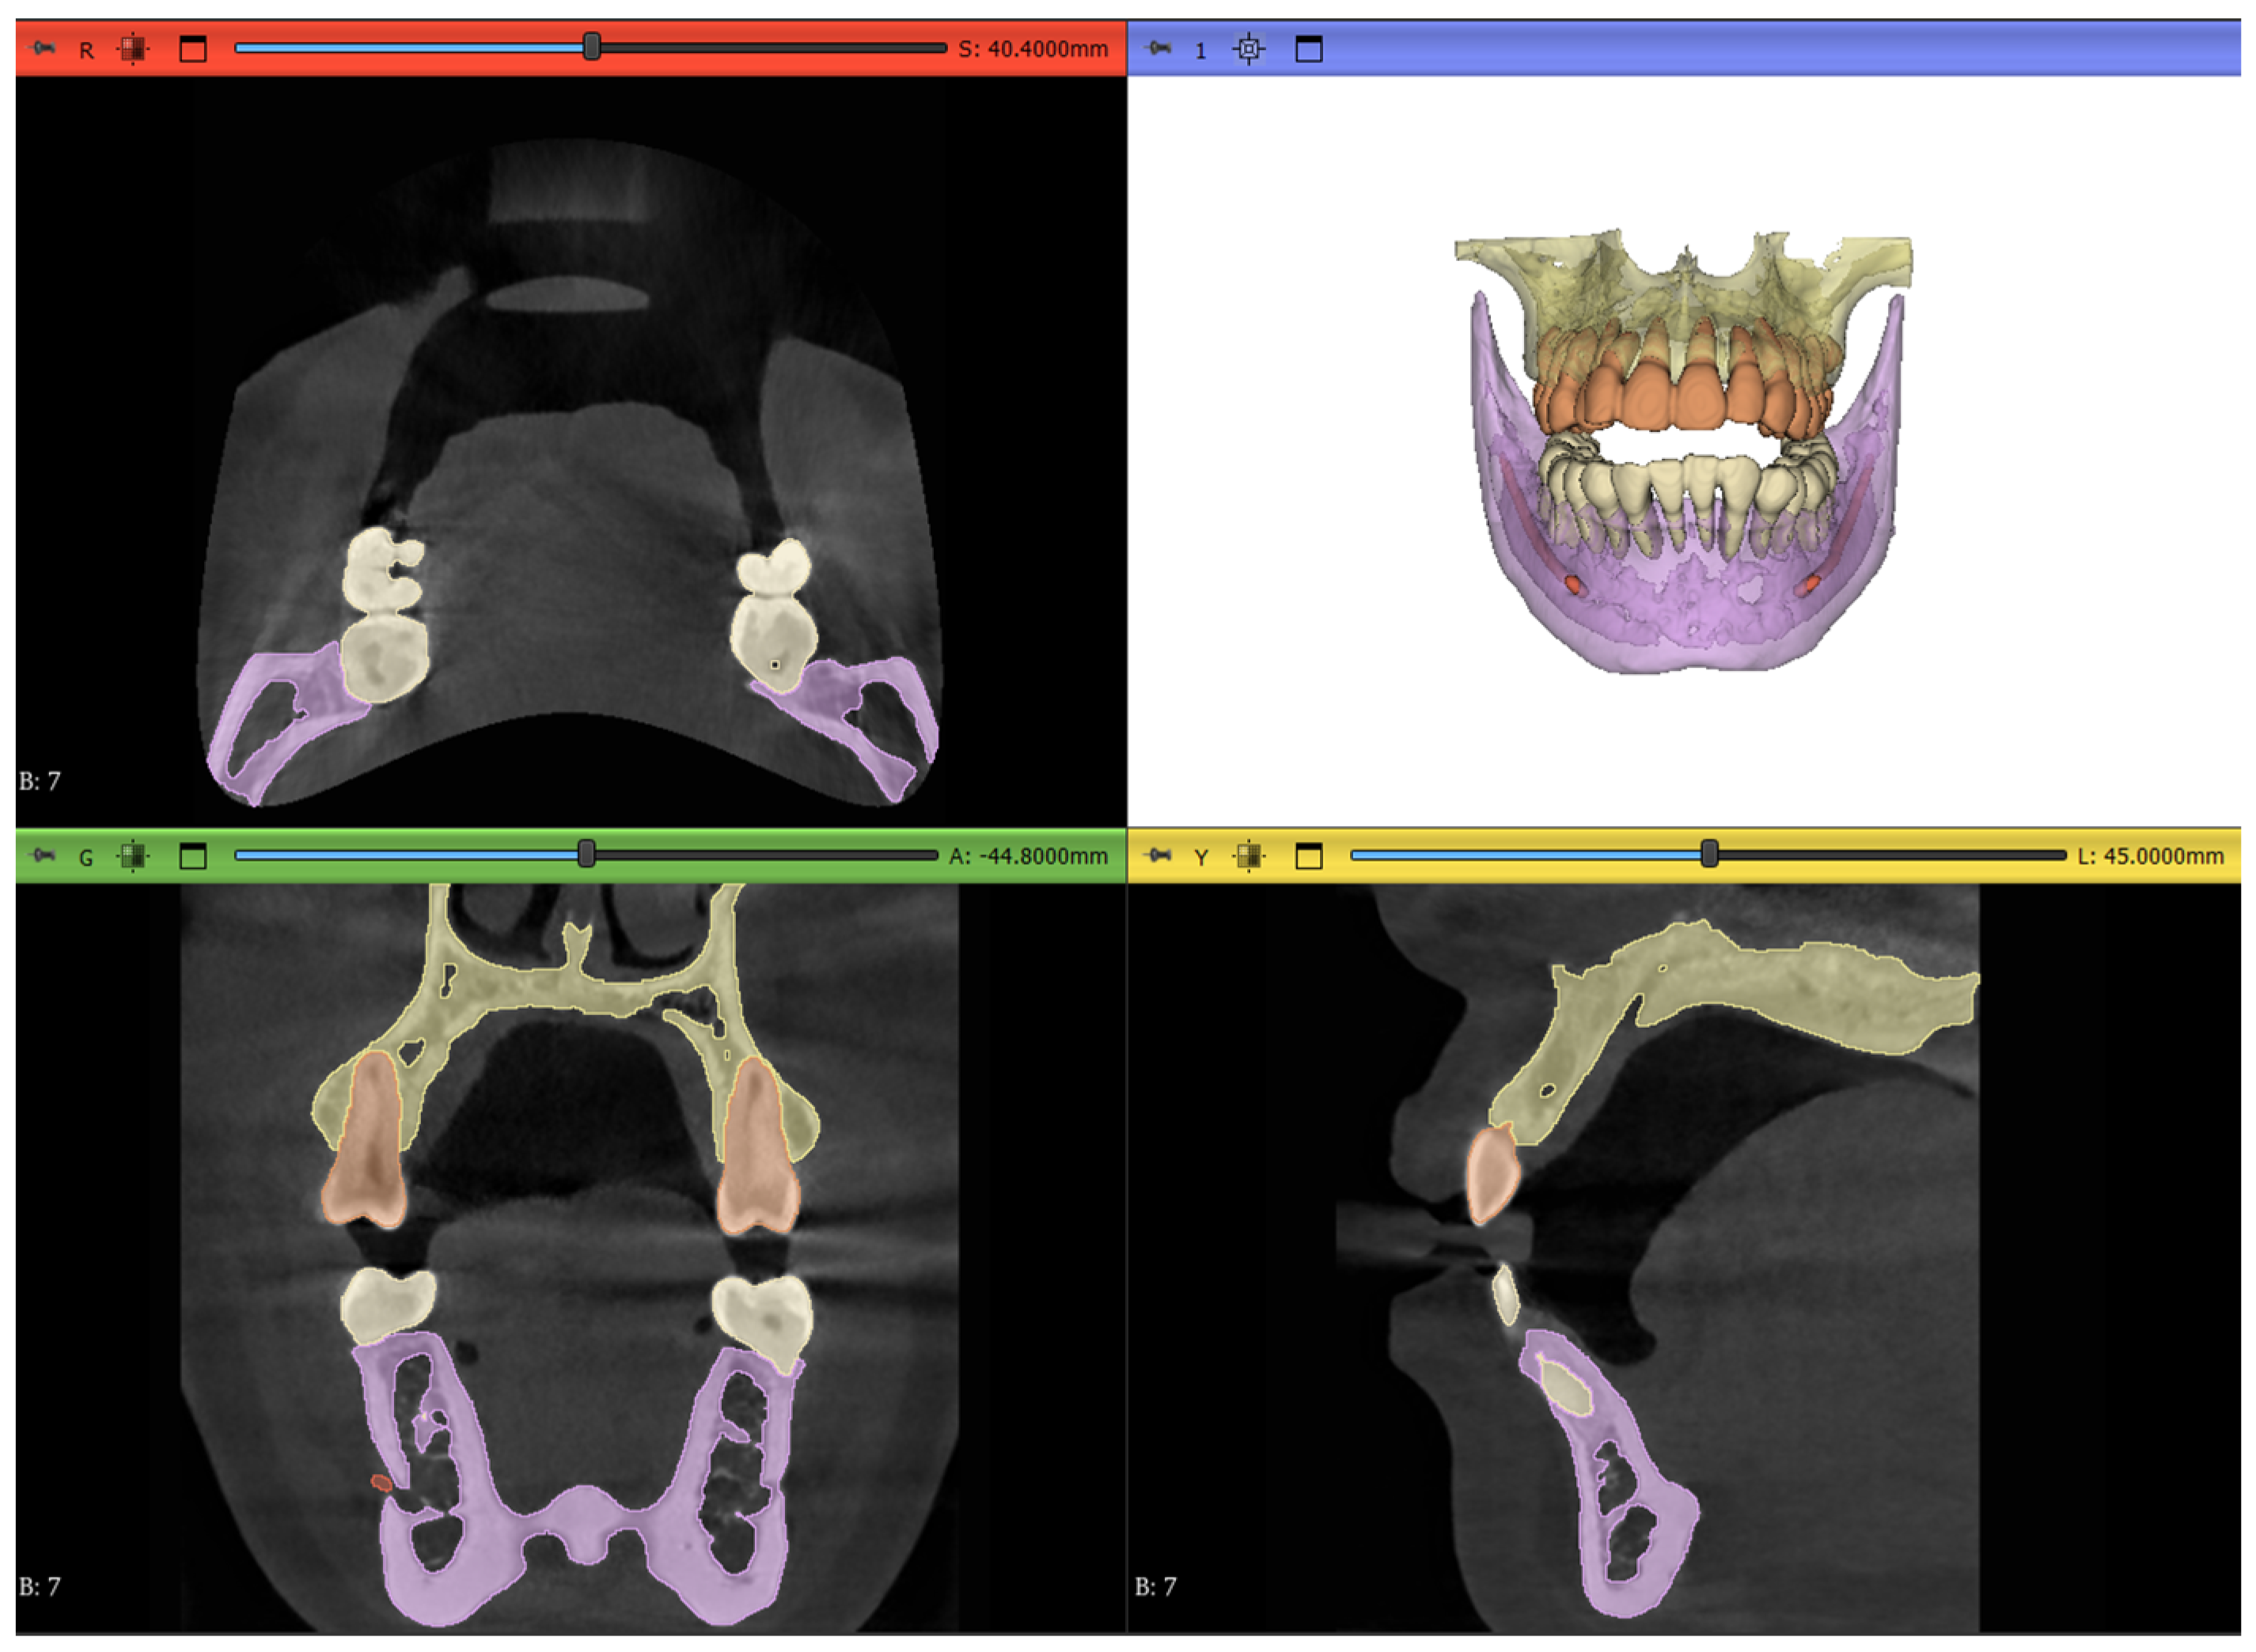

- Maxilla and upper skull

- Mandible

- Upper teeth

- Lower teeth

- Mandibular canal

2.8. Post-Processing